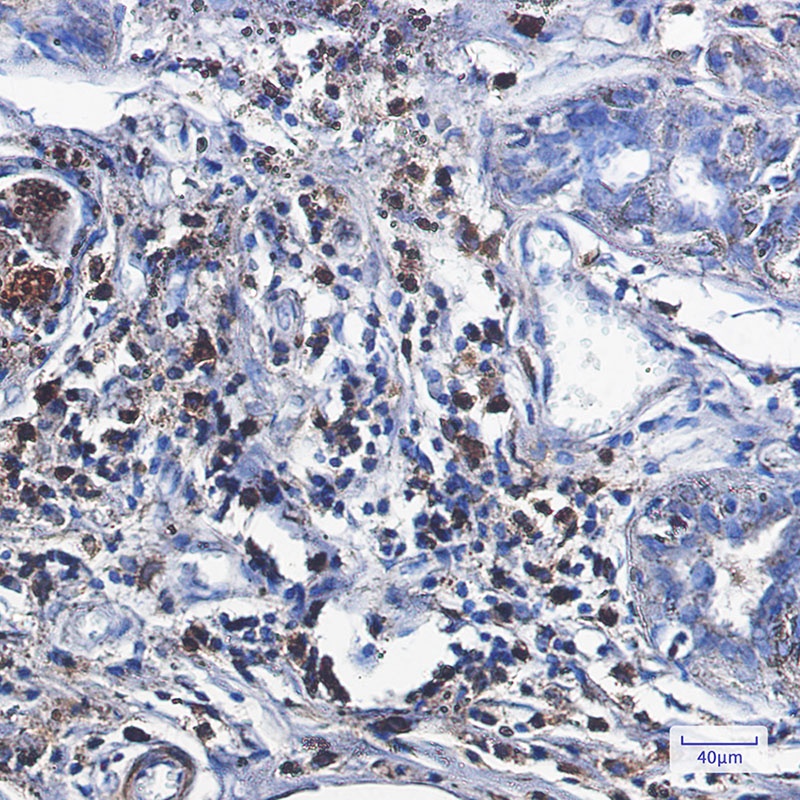

Immunohistochemistry of Catalase in paraffin-embedded Human breast cancer tissue using Catalase Rabbit mAb at dilution 1/1.